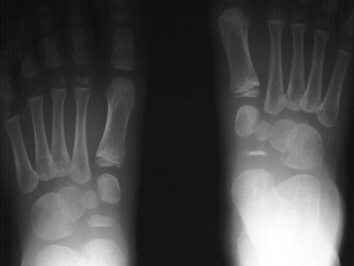

RADIOGRAPHS : AP, lateral and oblique views bilateral feet demonstrate

bilateral avascular necrosis of the navicular.

- flattening of the navicular

- narrowing of the navicular AP diameter in the lateral view

- irregular rarefaction and sclerosis

- irregular ossification of the navicular is seen in normal feet

- diagnosis of Kohler's disease should only be made when symptoms are

present